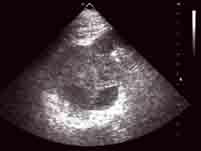

选项 A.B超常表现为不均质的中低回声实性肿块,但体积小的肾癌有时表现为高回声 B.IVU可见肾盏肾盂出现不规则变形、狭窄、拉长、移位或充盈缺损 C.CT对肾癌的确诊率不高,是目前诊断肾癌最可靠的影像学方法 D.肾错构瘤的脂肪成分表现为强回声,CT扫描呈负值,容易鉴别 E.B超、CT不能确诊的肾癌可作肾动脉造影检查

答案 C